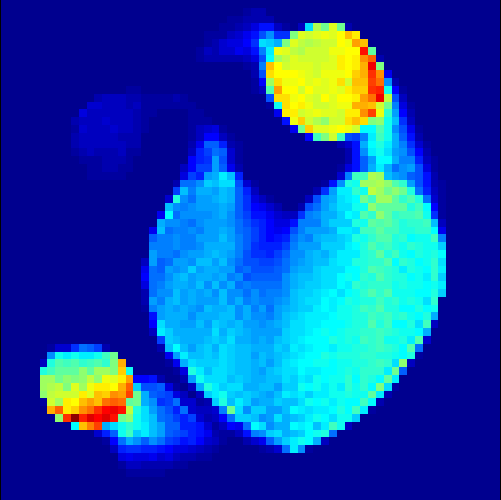

5.2 Monte Carlo Simulation

In order to test the behaviour of the proposed method in a more realistic, random-based test case, we performed a Monte Carlo simulation for dynamic SPECT imaging. First, we created a simple image phantom consisting of an outer and two inner circles which represents the structure of the region of interest (see figure 8(a)). Within those regions we assumed concentration curves over a time period of 90 time steps as displayed in figure 8(b). Based on the tracer intensity in an image frame at each time step, we created a variable number of random decay events (where the number is proportional to the average concentration in one pixel in the whole image frame per time step) with a probability proportional to the concentration in every subregion. They are detected by a virtual double head gamma camera rotating around the patient by 46 degrees per time step, which consists of 374 detector bins. Every simulated decay event is projected onto the scanner and counted by the corresponding detector bin.

In two different tests we fixed the number of events counted by the detector equal to (resp. ) times the average concentration in one pixel. The resulting sinogram images of the accumulated counts in each bin are shown in figure 9.

Based on the sinogram data we applied the proposed algorithm in order to reconstruct the original image sequence. The results for both test cases are shown in figure 10.

As one can see, the method is able to reconstruct the regions properly, even in case of a low count number. Within a number of iterations (average of 100 outer and 10000 inner iterations), the algorithm presents a reasonable reconstruction of the region of interest and the corresponding regional tracer concentration curves. Here, the parameters were not optimized as in the case of the synthesized data sets in the previous section, but kept fixed as , and . With futher optimized parameter values one could possibly provide even better results.